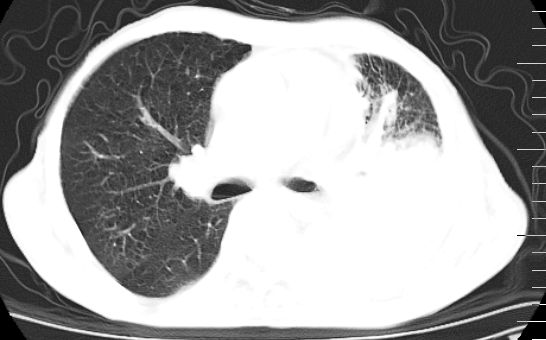

标题: CT10141:男、84岁,咳嗽、咯血1年。 [打印本页]

标题: CT10141:男、84岁,咳嗽、咯血1年。

支持左侧中央型肺癌伴下叶肺不张\\纵隔淋巴结转移.左侧包裹性胸腔积液\\心包积液.左侧少量胸腔积液..慢性支气管炎伴部分间质纤维化.

支持:左侧中央型肺癌伴下叶肺不张\\纵隔淋巴结转移.左侧包裹性胸腔积液\\心包积液.左侧少量胸腔积液..慢性支气管炎伴部分间质纤维化.另:支气管分支根部明显阻塞 狭窄,内膜凸凹不平,提示内膜增生物。

咯血病史较长,左肺下叶实变,体积未明显缩小,隐约可见血管影及坏死阴影,双肺门及纵隔淋巴结增大,心包增厚积液,纵隔右移位,单侧胸腔积液,首先考虑:大叶型肺泡癌伴纵隔心包转移。